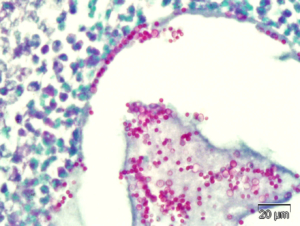

Right: High magnification of photomicrograph demonstrating conidia in a fungal granuloma in the sinus of a rabbit (PAS)

CBI has developed and validated a surgically-induced model of either invasive or noninvasive nasal aspergillosis infection in rabbits. In this model, a fungal infection in the sinus is established using proprietary methodology, and then various modalities for treatment are assessed. Studies are custom designed specifically for each sponsor and test article.